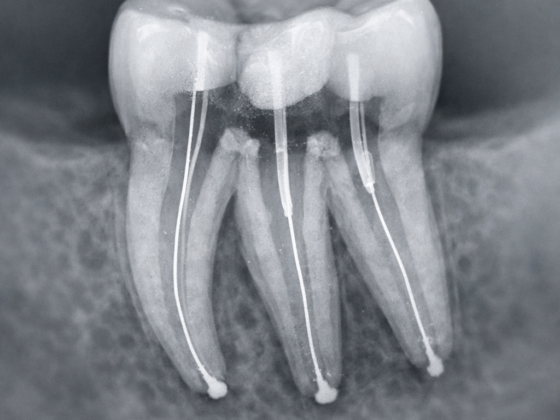

Endodoncia Multiradicular

Tratamiento de conductos en muelas con varias raíces que permite eliminar la infección del interior del diente, aliviar el dolor y conservar la pieza dental, evitando su extracción.